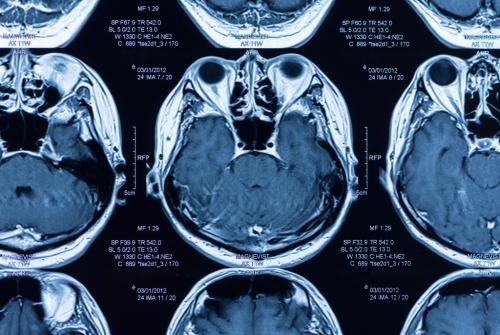

MR da vücudumuzdaki hidrojen protonları uyarılarak sinyal alınır. Sıvı yoğun ortamda hidrojen protonları hareketli olur, bu hareket diffüzyo...